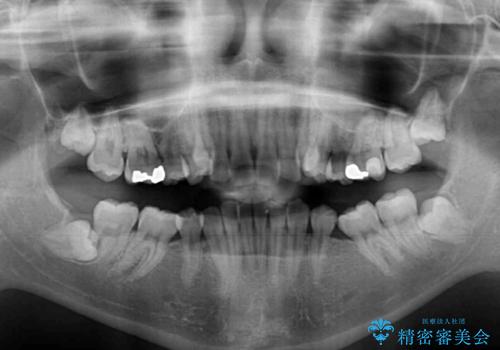

下顎小臼歯の欠損により過蓋咬合となっていたため、下顎は臼歯を起こすことで咬み合わせを改善し、八重歯は第一小臼歯2本を抜歯し、補助装置を使用して速やかに改善することとしました。

著しい過蓋咬合の改善が必要であった割には、治療期間は2年強と標準的でした。